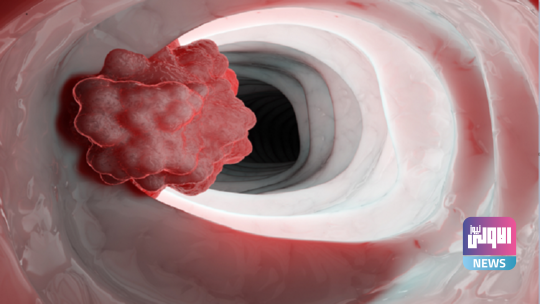

ماهي الخضروات التي تزيد من خطر الإصابة بسرطان المريء؟

أعلن الدكتور أندريه فوروبيوف، أخصائي الأورام، أن الخضروات المخللة تضاعف من خطر الإصابة بسرطان المريء.

ويشير الأخصائي، إلى وجود علاقة متبادلة بين سرطان المريء والخضروات المخللة المفضلة لدى الكثيرين.

ويقول، “تشير نتائج الدراسات العلمية إلى أن الخضروات المخللة. تزيد من خطر الإصابة بسرطان المريء بمقدار ضعفين”.

ويضيف، يحتل سرطان المريء المرتبة الرابعة عشرة من حيث الانتشار بين البالغين.

وتشير نتائج الدراسات التي أجريت على القوارض لتحديد أسباب تحول الخضروات المخللة إلى مواد مسرطنة، إلى حدوث تغيرات وتحولات نشطة فيها تسبب تضخما وخللا في تسيج ظهارة مريء القوارض ونشوء أورام.